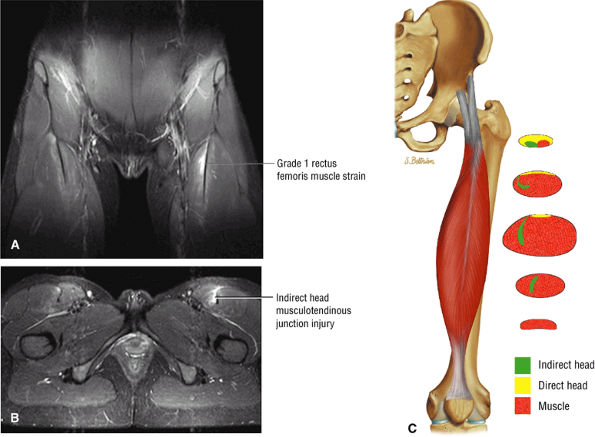

FIGURE 3.6 ● RECTUS FEMORIS The rectus femoris flexes the thigh (hip) and extends the leg (knee). Of the four quadriceps muscles (the vastus lateralis, vastus medialis, vastus intermedius, and rectus femoris), only the rectus femoris has an origin that crosses the hip joint. Soccer, football, and basketball players and track and field athletes are at risk for distal musculotendinous junction injuries and proximal intrasubstance tears of the musculotendinous junction of the indirect head of the rectus.

Grade 1: Minimal disruption of the musculotendinous junction (Fig. 3.106). Clinically, a grade 1 strain may simply result in a muscle spasm or cramp.

Grade 2: A partial tear with some intact musculotendinous fibers (Fig. 3.107). Clinically, there is discomfort during sports activity or training, but it usually resolves with rest.